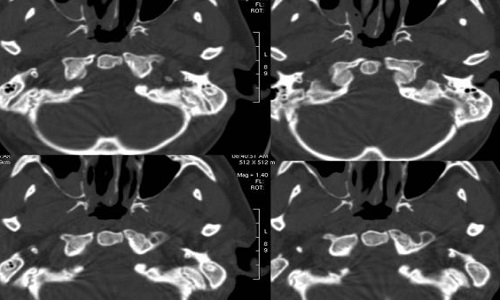

放射学检查以枕骨大孔区为中心的颅-颈正侧位片、体层摄片、前后位开口摄片(检查寰、枢椎)、颅底摄片(检查斜坡、齿状突)等颅脑平片。通常颅-颈侧位片即可确诊是诊断颅底凹陷症最简单的方法。必要时可行CT扫描、矢状面重建则对枕骨大孔区的畸形观察更为清楚另外可根据病情选择脊髓造影气脑造影脑室造影和脑血管造影等。

2、CT扫描主要是显示脑组织及脑室的改变有时可行脑室造影CT扫描在脑室内注入非离子水溶性造影剂后行CT扫描可观察到脑室大小中脑水管是否通畅及第四脑室及脑干的改变,并可勾画出小脑扁桃体下缘的位置

3、MRI检查MRI是诊断本病最好的检查手段之一,尤其在矢状位可清楚的显示中脑水管第四脑室及脑干的改变小脑扁桃体下疝的程度及颈髓受压的情况便于决定手术治疗方案